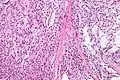

| Micrograph of a myoepithelioma. H&E stain. | |

The myoepithelial cells may be spindled, plasmacytoid, eithelioid or clear. Tubules or epithelium are absent, or present in a small amount (<5%) by definition. Tumours with myoepithelial cells and a large amount of tubules are classified as pleomorphic adenomas (which must also contain the characteristic chondromyxoid stroma, which is normally absent in myoepithelioma).

Low mag.

High mag.